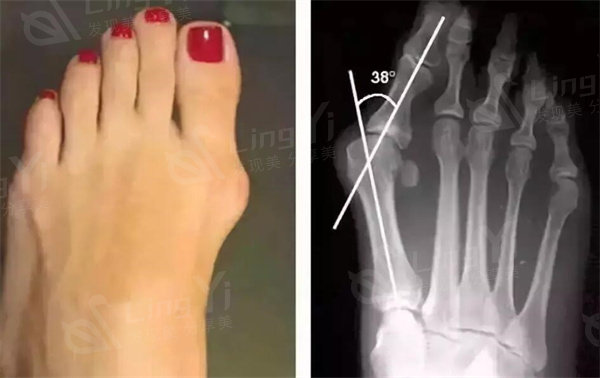

拇外翻是一种足部畸形,它通常是指大拇趾偏离正常位置向外向脚的一种情况。这个问题可能会导致足部疼痛、行走困难和其他问题。那是否有必要进行拇外翻手术呢?我们来看一下以下几点:

拇外翻是一种足部畸形,它通常是指大拇趾偏离正常位置向外向脚的一种情况。这个问题可能会导致足部疼痛、行走困难和其他问题。拇外翻手术是一种常见的治疗方法之一,下面是其利弊的介绍。